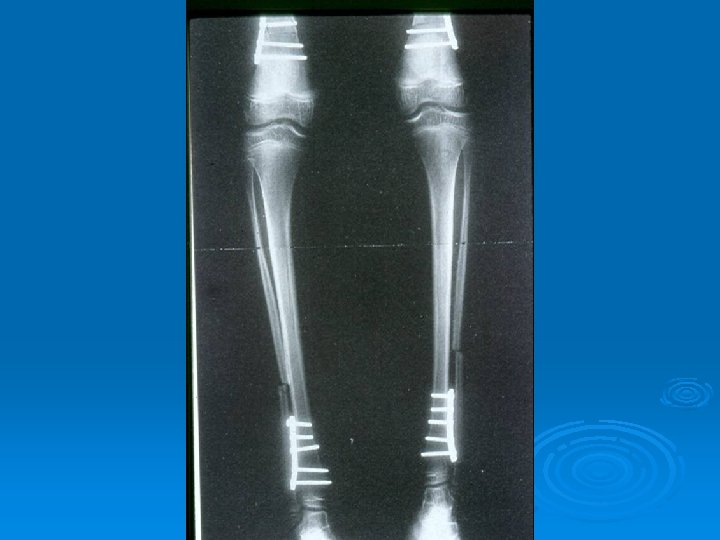

Deformities Lower limb : Ø Hip adduction/flexion/internal rotation Ø Knee flexion Ø Feet equinus / varus or valgus Ø Gait scissoring Spine : kyphoscoliosis

Management Goal of Surgery : Ø Ø Ø Decrease spasm Release of contractures Correct deformities Rebalance muscles Stabilize flail joints

Management Options of Surgery : Ø Ø Ø Ø Neurectomy Tenoplasty Muscle lengthening (Recession) Tendon Transfer Bony surgery Osteotomy/Fusion Spinal surgery